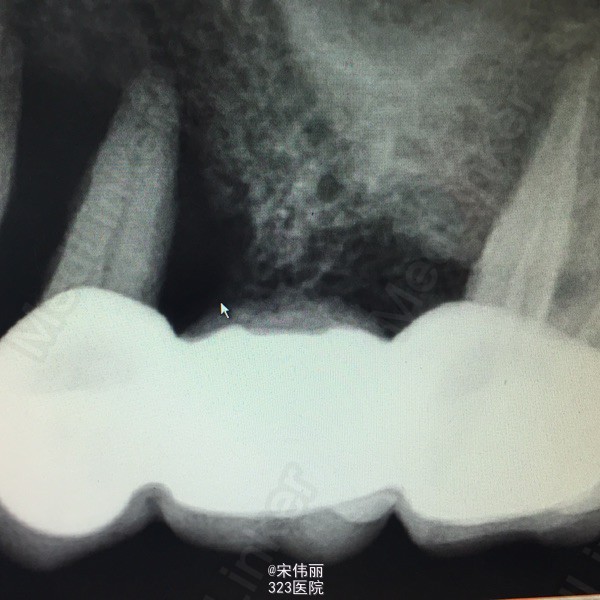

25、26、27冠修复,松动3度,24松动3度,龈袋探深7mm左右,12残根,14、15、16冠修复,下颌重度磨耗 x线示:24、25牙槽骨吸收至根尖

诊断:24、25重度牙周炎 建议:24、25、26、27拔除 处理:全身状况稳定,24、25、26、27“必”麻下顺利拔除,搔刮牙槽窝,牙槽窝复位,缝合4针,咬干棉球止血。